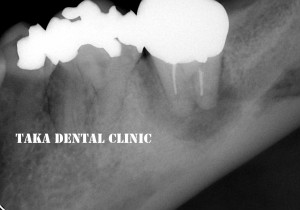

↑初診時

歯肉から膿が出て、咬むと痛む、若干歯が動いていると来院されました。確かにレントゲン写真では、大きな病気が出来ています(根の周りの黒い影)。